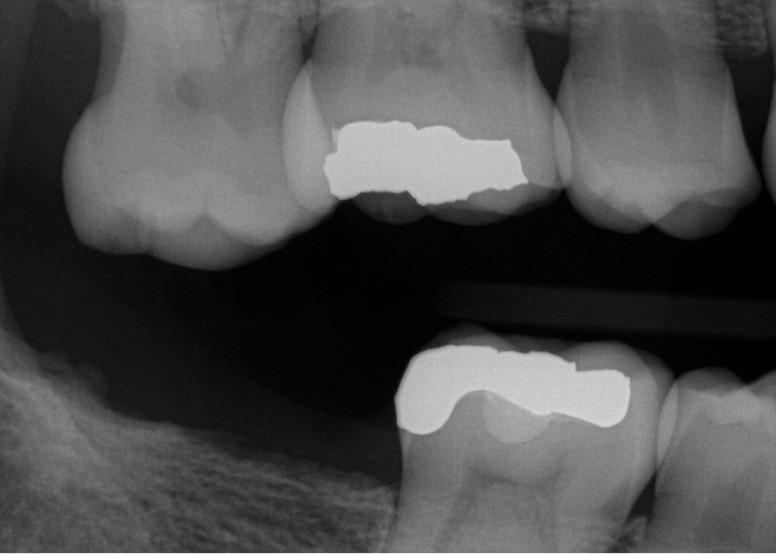

Fig 6. Patient No. 3 presented for an implant restoration at site No. 31 to eliminate pain due to chewing on the ridge from extruded tooth No. 2. Tooth No. 2 was equilibrated to eliminate the patient’s symptoms. In some patients, super-eruption can be severe enough to preclude an implant restoration due to a lack of restorative space.

Figure 6

If a patient chooses not to replace a missing second molar but desires to preclude over-eruption of an opposing molar, a preventive restoration may be fabricated. Examples of such a restoration may include bonding to an adjacent tooth, a metal splint bonded to adjacent teeth, a removable prosthesis, an extended prosthetic length of arch with a cantilever, or the use of a nightguard. This could prevent molar hyper-eruption, which may predispose an individual to plaque retention that could cause caries or periodontitis (Figure 5).40 Potential loss of interocclusal space also must be addressed with patients, because extraction of a second molar can result in migration of an unopposed tooth, which may complicate the replacement of the antagonist (Figure 6). Importantly, a super-erupted tooth may need to be significantly reduced before fabricating an opposing implant prosthesis, or an extruded tooth may need to be devitalized, crown-lengthened, or intruded to provide proper interocclusal space for a restoration.